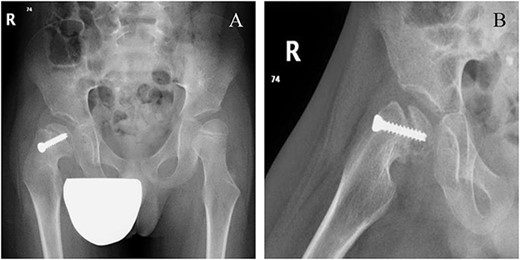

Six weeks following post-operative fixation: (A) pelvic anterior–posterior radiograph and (B) pelvic frog-leg lateral view radiograph.